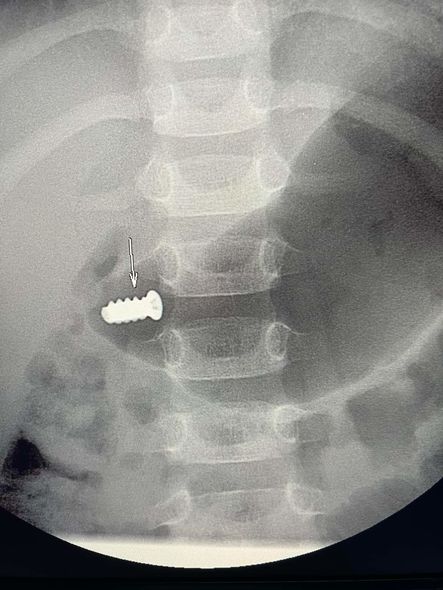

Belə ki, azyaşlının mədəsində yad cisim, şurup parçası aşkar edilib.

Məlum olub ki, körpə şurup qırığını götürərək burnuna qoyub. Daha sonra metal cisim burun-udlaq vasitəsilə qida borusuna, oradan isə mədəyə düşüb.